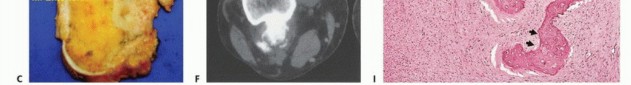

Imaging Set 1: Pathophysiology and Staging Fundamentals

- Plain Radiography: The cornerstone of initial evaluation. It accurately predicts the diagnosis in over 80% of extremity bone tumors. It defines the lesion's location, zone of transition (narrow/sclerotic = benign/slow; wide/permeative = malignant/aggressive), cortical destruction, and periosteal reactions (Codman triangle, onion-skinning, sunburst pattern).

- Computed Tomography (CT): The modality of choice for assessing fine osseous detail, cortical integrity, and matrix mineralization. Thin-slice (≤1 mm) helical CT allows for precise 3D reconstructions. Intravenous contrast is essential to delineate the relationship of the soft tissue mass to major vascular bundles. Chest CT is mandatory for staging to rule out pulmonary metastases.

- Magnetic Resonance Imaging (MRI): The gold standard for evaluating the local extent of the tumor. It accurately defines the intramedullary extent (allowing calculation of bone resection levels), soft tissue extension, joint involvement, and the presence of skip metastases. T1-weighted images best define marrow replacement; T2-weighted and STIR sequences highlight peritumoral edema and the soft tissue mass. Contrast enhancement differentiates cystic from solid components and clarifies neurovascular proximity.